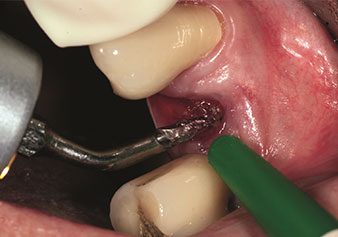

Gestione alveolare

Un’applicazione che viene spesso sottovalutata è l’estrazione atraumatica di radici di denti o frammenti di radici nell’ambito della gestione alveolare. I periotomi sottili, che sono attualmente disponibili in due versioni (EX1 ed EX2 di W&H), possono essere, inoltre, utilizzati per rimuovere con facilità denti che hanno precedentemente subito uno specifico trattamento endodontico o con radici anchilosate. Ne consegue l’estrazione di alveoli in cui i tessuti duro e molle sono entrambi completamente intatti in quanto è generalmente possibile evitare la riflessione.

Ciò pone le basi ottimali per un trattamento con impianto immediato o successivo (Figure 1 e 2 inserite grazie alla gentile concessione del Dott. Torsten Conrad, Bingen a. Rhein).

Foto: © Dott. Torsten Conrad (Bingen a. Rhein)